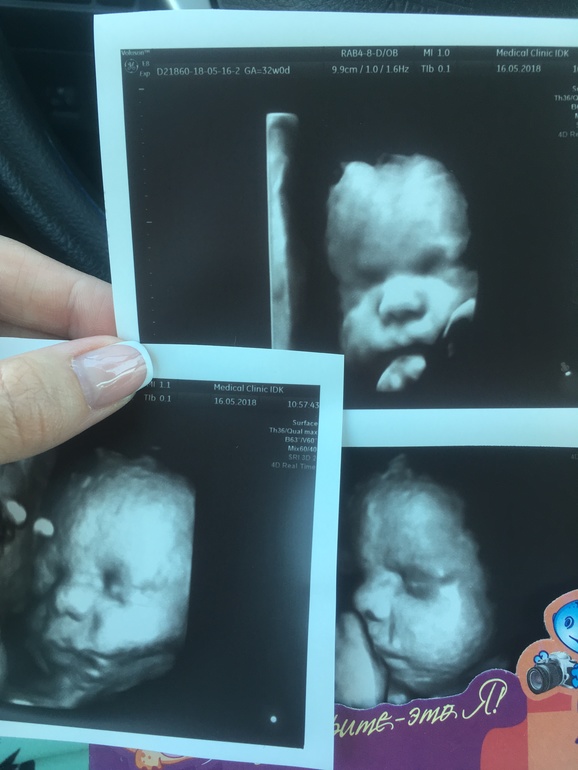

Третья на кого похожа?

УЗИ, КТГ, доплерПо мне так на сына, прям копия 🤗

Срок 32 недели